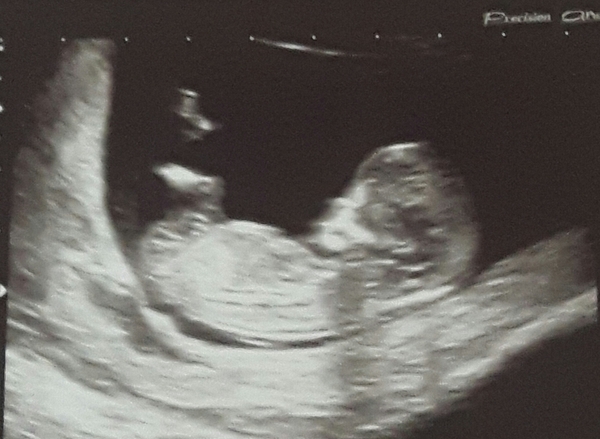

Finally saw baby, first scan at 11 weeks (or 13 by their crazy calculations).

I know how all of you awaiting scans are feeling, I've had this constant low anxiety for about 4 weeks now. But all is well! I think i can relax and be happy now, after all if baby made it to this point without event, or surveillance, no reason to think s/he won't continue to do so.

Hope all other people having scans today had a good experience too Flowers

dontbeblue lovely scan! Why are their calculations crazy? I would be so pleased to be further along than I thought!

We had a great first scan yesterday and saw the little one wriggling away (through my crazy tears of relief).

These scan pics are amazing, everyone!